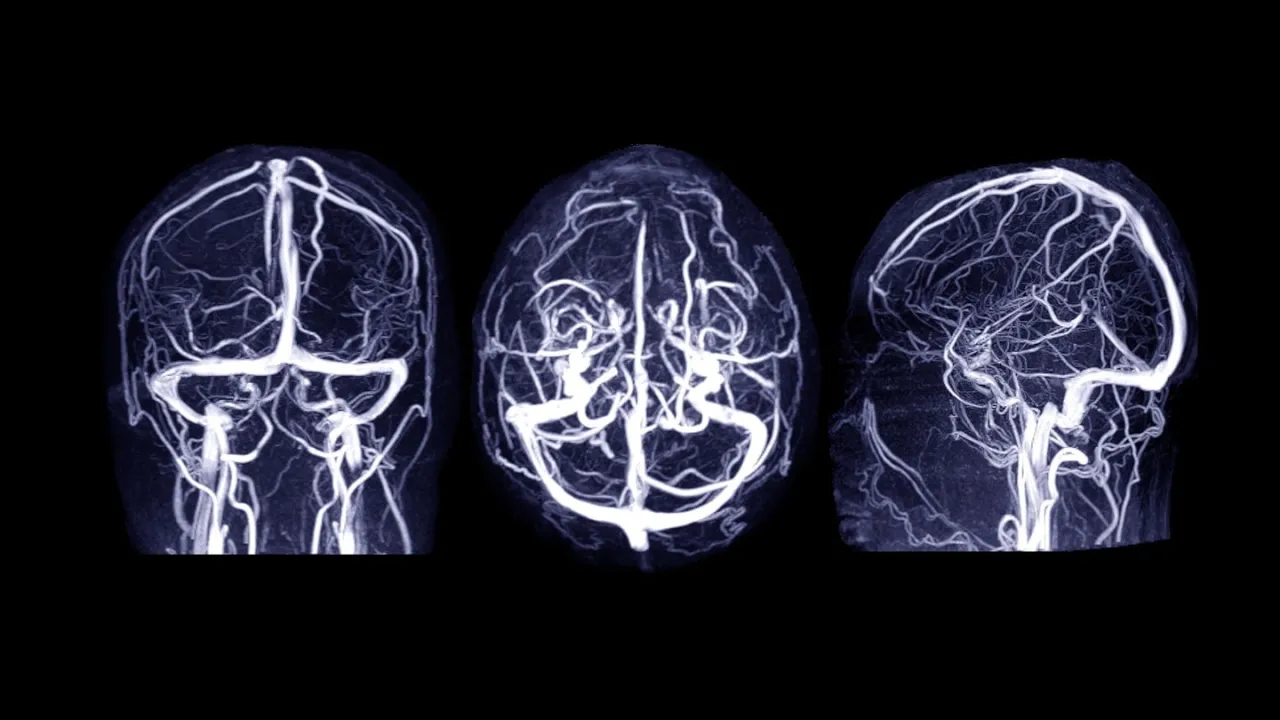

Weitere Untersuchungen: Wann eine Angiographie oder MRT notwendig wird

Um die genaue Ursache der Blutung zu finden, können weitere bildgebende Verfahren notwendig sein. Bei Verdacht auf ein Aneurysma oder eine andere Gefäßfehlbildung wird oft eine CT-Angiographie durchgeführt, bei der Kontrastmittel die Blutgefäße sichtbar macht. In manchen Fällen kann auch eine Magnetresonanztomographie (MRT) sinnvoll sein, um das Hirngewebe detaillierter zu beurteilen.